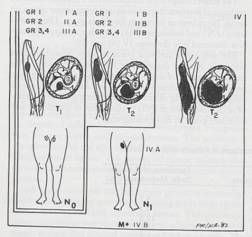

TO: Stadializare

SPM: Stadializare

- T

: T1 vs T2 = <5 vs >5 cm

- N : N0 vs N1

- N1

M1

SPM:

Stadializare